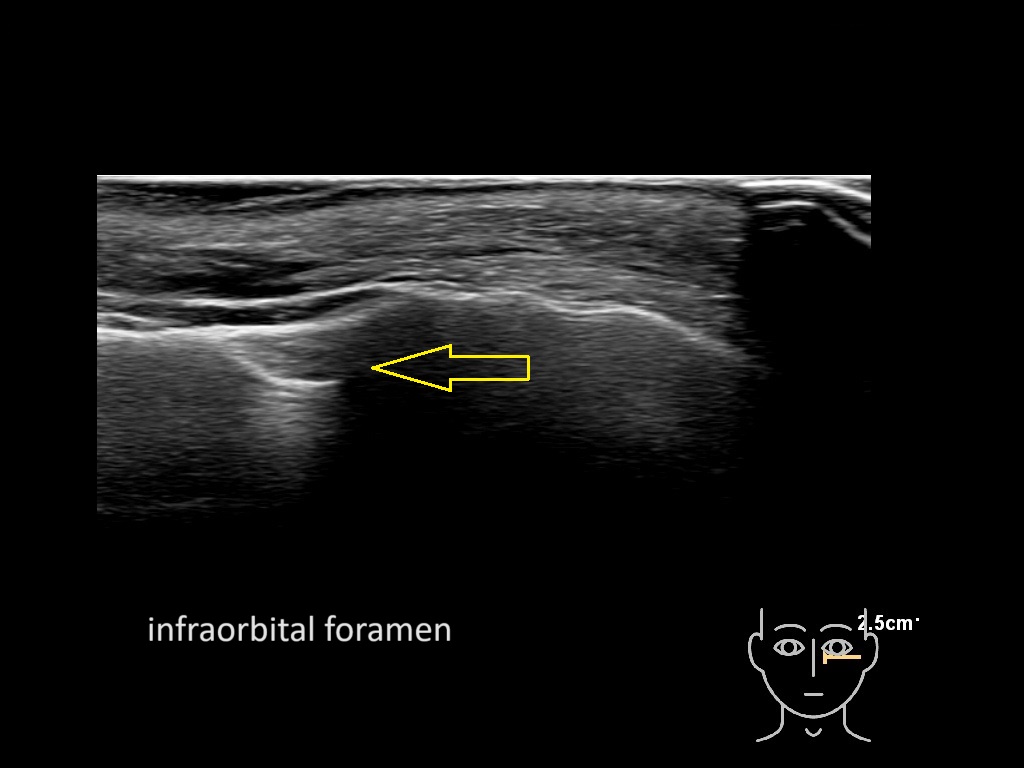

Study the first image to recognize the different layers. If you are sure about the layers, swipe to the second image to view the answer (if applicable).